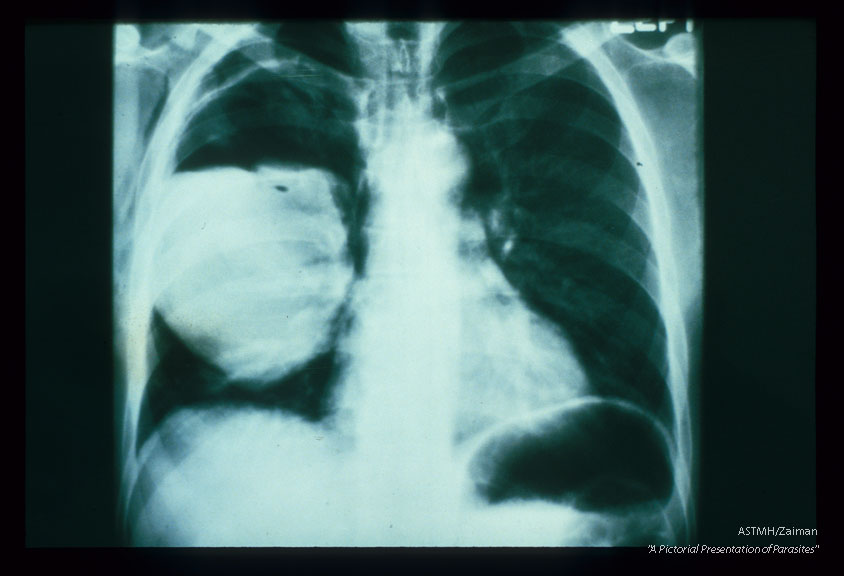

Frontal and lateral chest x-rays. A huge partially empty white cyst is present in the right lung of this patient. It's upper limits are marked by a white pencil-like line of calcium, Above the white fluid and below the white penciled line, the cyst is filled with air (black). This indicates communication between the cyst and a bronchus. Usually an air-fluid interface would be a neat line. In echinococcosis, the line is irregular due to floating collapsed membranes (from the dome of the cyst) and floating daughter cysts. This is the classic floating lily sign of pulmonary echinococcosis.

Echinococcus granulosus